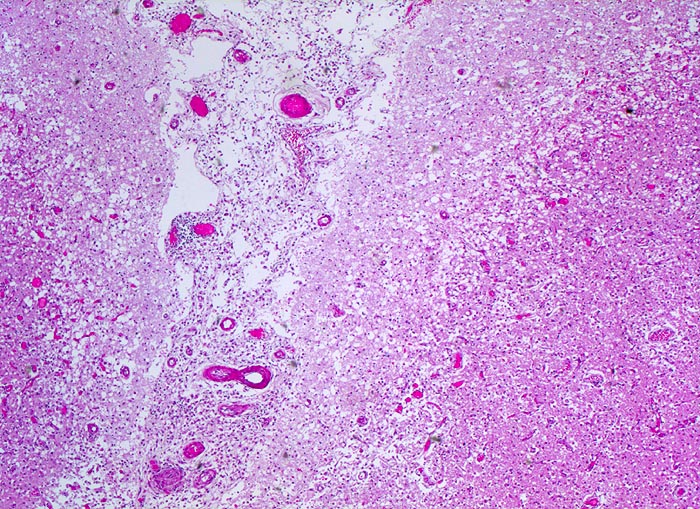

• Links unten leptomeningeale Gefässe mit partiell rekanalisierten alten thromboembolischen Verschlüssen.

• Unscharfe Mark-Rindengrenze im Bereich der nekrotischen Rinde.

• Spongiotische Auflockerung der Hirnrinde (hellere Areale).

• In der Hirnrinde sind hypereosinophile nekrotische Neuronen mit stark abgeblassten Zellkernen erkennbar.

• Perivaskuläre Ansammlungen von phagozytierenden Fettkörnchenzellen mit reichlich lipidhaltigem Zytoplasma und ovalen Kernen sowie wenige extravasierte Erythrozyten.